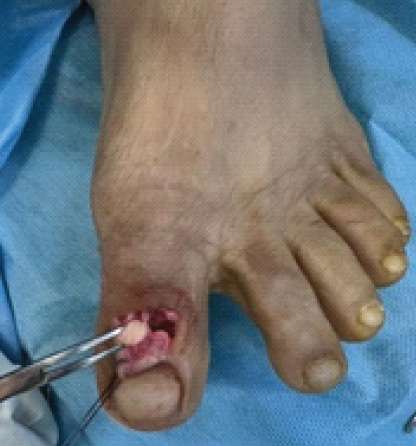

The interposed sesamoid was carefully excised (Fig. 4). Subsequent intraoperative joint ranging confirmed the absence of bony or soft-tissue blocks. Despite this, spontaneous joint reduction was not achievable, likely due to periarticular soft-tissue contractures associated with the subacute presentation.

Figure 4: The intraoperative removal of the incarcerated sesamoid between the interphalangeal joint of the great toe.